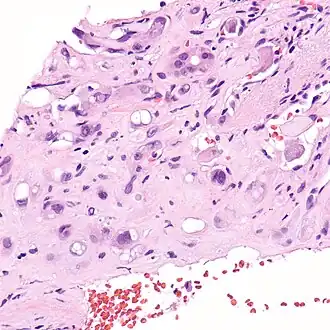

| Micrografia de um hemangioendotelioma epitelióide do fígado. | |

Hemangioendotelioma epitelióide (HEE) é um raro tumor vascular, inicialmente descrito por Sharon Weiss e Franz Enzinger, o qual tanto clinicamente quanto histologicamente é intermediário entre o angiosarcoma e o hemangioma. No entanto, alteração genética distinta, diagnóstica da patologia, foi recentemente descrita para HEE, indicando que ele é realmente uma entidade separada tanto do angiosarcoma quanto do hemangioma.

O hemangioendotelioma epitelióide é um sarcoma de partes moles e é geralmente considerado um câncer vascular, na medida em que as células "lesionais" expressam marcadores de superfície típicos de células endoteliais (células que revestem o interior dos vasos sanguíneos). Originalmente, foi descrito como ocorrendo mais comumente nas veias das extremidades (braços e pernas) e em dois órgãos, o fígado[1] e os pulmões. Desde então tem sido descrito em órgãos por todo o corpo. Além do fígado e dos pulmões, os ossos e a pele foram os órgãos mais freqüentes.